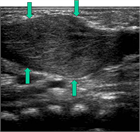

1. 乳児期に認められる頚部腫瘤が、エコー上胸鎖乳突筋の腫脹として捉えられ、正常の筋に認められる層状の筋内部エコー像に乱れが生じている場合には、筋性斜頚と診断する。

1. 一般に筋性斜頚は乳児期に診断されるが、その時期に診断されずに年長で斜頚位を呈している場合には、ときとして診断に難渋することがある。こういった場合には、胸鎖乳突筋の拘縮を触知できない場合でもエコー像では左右差を認めることが多く、診断に有用である。